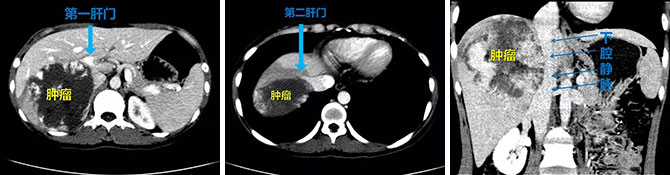

患者入院后利用目前肝胆外科医疗新技术:肝脏肿瘤及肝内管道的3D重建,重建结果提示肿瘤巨大,长径达13cm,几乎占据患者整个右半肝,周围肝实质及肝内管道受压明显,肝脏的第一、第二及第三肝门均受到压迫。经过肝胆外科团队详细术前系统的评估、规划和讨论,为患者制定了微创的荧光腹腔镜肝血管瘤切除术。

10月27日手术正式开始,在麻醉团队密切合下,肝胆外科团队术中运用当前先进的荧光腹腔镜联合腹腔镜超声实时导航,抽丝剥茧,采用目前最先进的Laennec包膜入路切肝技术,游离显露出肝脏的第一、第二及第三肝门,保护了重要的肝脏管道,完整切除肝右后叶巨大血管瘤,保留了尽量多的肝实质。